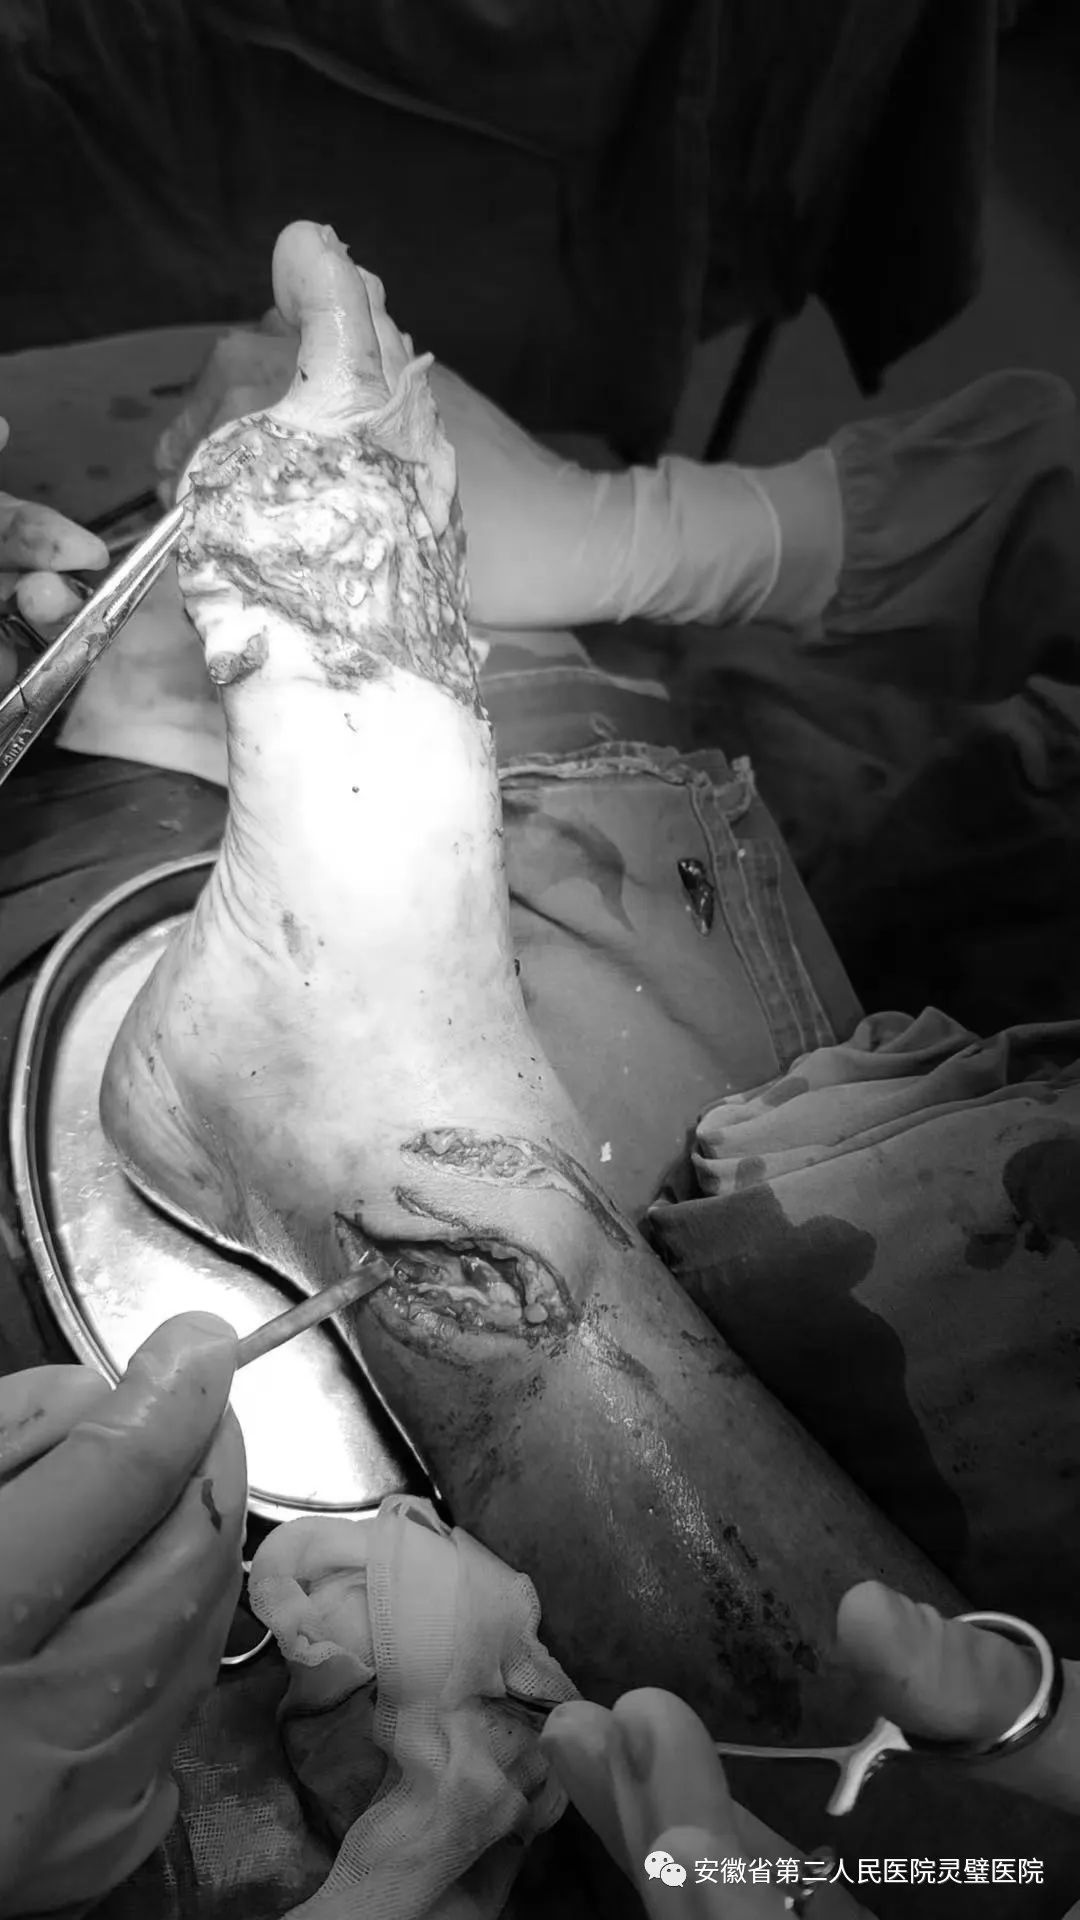

皮带搅伤致右足广泛脱套伤

患者男73岁。在家干农活时不慎被皮带搅伤右小腿及足部,急诊手足外科检查创面较大,右小腿远端内侧可见斜形挫裂伤,周围皮肤碾压挫伤,创面污染,皮缘错灭,骨质外露。右足背广泛脱套,自足中部直至远端,皮肤挫伤明显,边缘血运欠佳,趾旋转挫裂,无血运,余四趾末梢血运欠佳。开通绿色通道,手足外科医生团队在麻醉、手术室全力配合下,为患者实施了撕脱皮肤原位回植+取皮植皮+KCI负压吸引术,手术过程顺利,术后恢复良好。